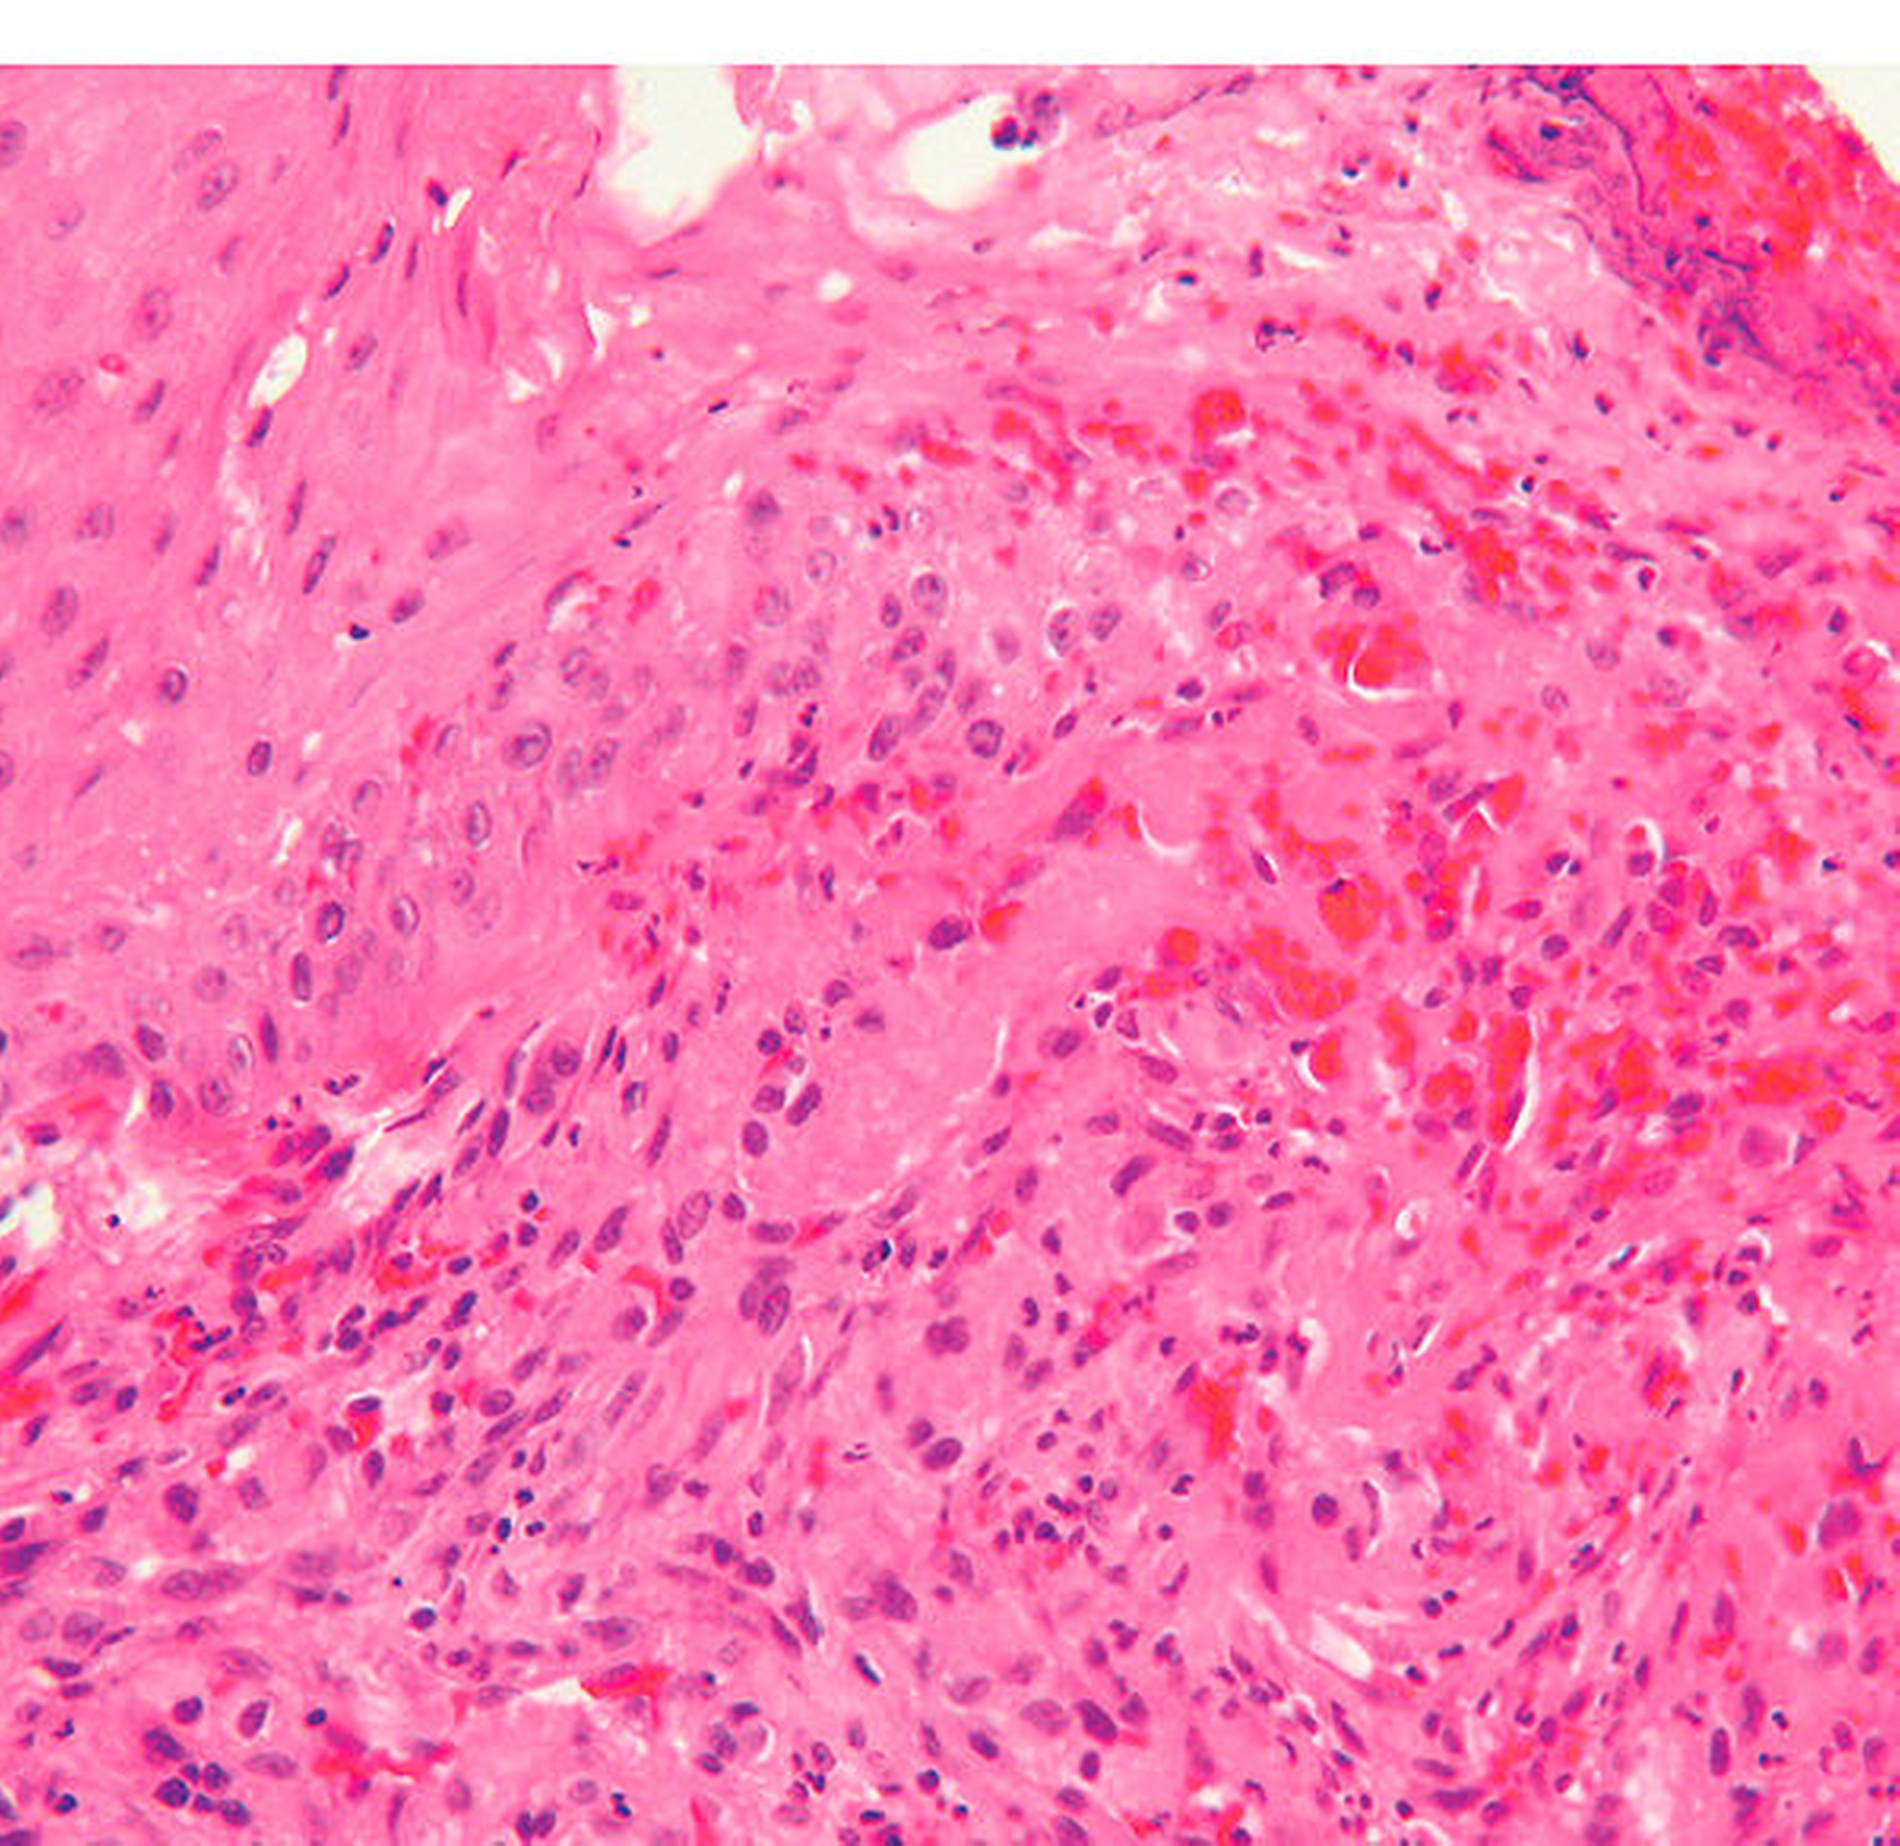

Histologisch finden sich bei jungen pyogenen Granulomen dünnwandige anastomosierte Blutgefäße in lockerem, ödematösem und mäßig zellreichem Stroma, wodurch diese rötlich erscheinen. Durch Verletzungen können diese Veränderungen sekundär fibrosieren, so dass die Farbe von rot nach rosa umschlägt. Die entzündliche Komponente kann unterschiedlich stark ausgeprägt sein, aber auch komplett fehlen.

Ätiologisch geht man beim pyogenen Granulom nicht von pyogenen Keimen, sondern von lokalen irritativen Faktoren aus. Besonders bei pyogenen Granulomen, die nicht auf der Gingiva zu finden sind, berichten Patienten über vorausgegangene Traumen. Histologisch handelt es sich um eine lobulär aufgebaute, kapilläre Gefäßwucherung [Klöppel et al., 2009].